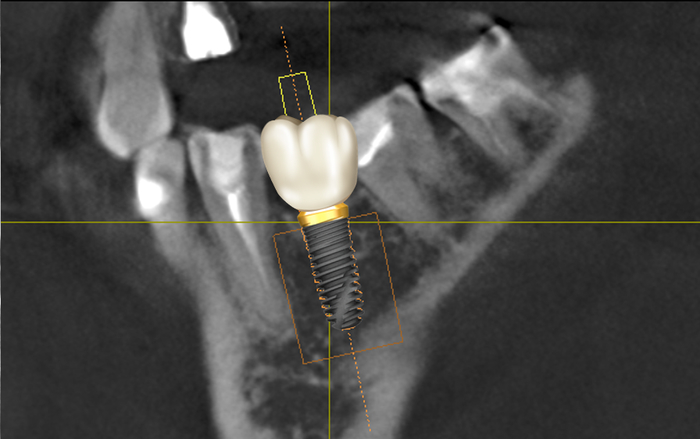

Имплантат в данной области должен располагаться примерно так:

В данном случае можно столкнуться с сложностями позиционирования имплантата, потому как наклон 7-го зуба препятствует правильному расположению сверла. Но это даже не самая большая проблема. Вся загвоздка в том, что в данном случае изготовить и установить коронку анатомический правильной формы будет невозможно. Ниже то, как (примерно) должен располагаться имплантат и коронка: